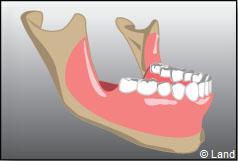

La partie osseuse autour de la dent enlevée aura tendance à se rétracter avec le temps, sauf si elle est réhabilitée avec un implant. Les extractions simples sont des actes à tarifs opposables remboursés par la Sécurité sociale.

Certaines dents n’arrivent pas à faire leur éruption sur l’arcade correctement, présentent un accès difficile (dents de sagesses), ont des racines divergentes ou très courbées, ou sont considérablement abîmées (carie importante par exemple). Aussi elles restent souvent en partie ou totalement incluses dans l’os. On procède alors à une extraction chirurgicale.